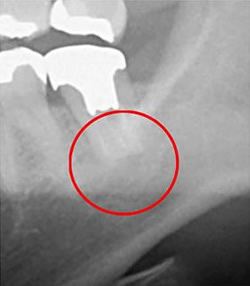

下に2枚の画像を並べています。左はCTで撮影したもの、右はデンタルレントゲンで撮影したものです。赤丸で囲った部分は同じ部位ですが、CTでは黒く影になっているのがはっきりと分かるのに対し、デンタルレントゲンではあごの骨によってはっきりと患部の状態が分かりません。

トラブルが起こっている部位を見逃してしまうと、必要な治療を施すことはできません。

患部の状態を適切に把握できるCTの導入は、精密・正確な治療には不可欠です。